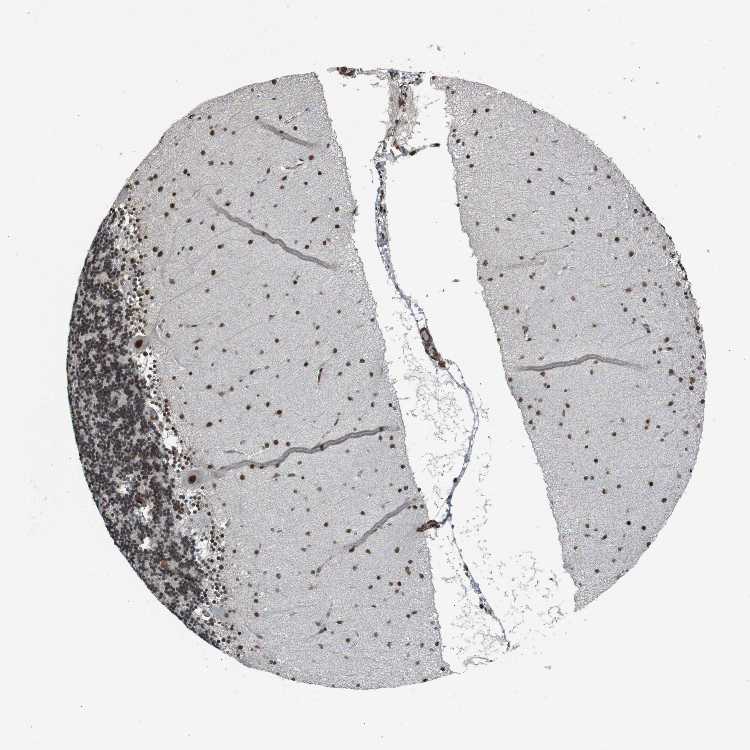

CEREBELLUM - Antibody stainingi

Antibody staining in the annotated cell types in the current human tissue is reported as not detected, low, medium, or high, based on conventional immunohistochemistry profiling in selected tissues. This score is based on the combination of the staining intensity and fraction of stained cells.

Each image is clickable and will lead to virtual microscopy that enables deeper exploration of all samples and also displays staining intensity scores, fraction scores and subcellular localization as well as patient and tissue information for each sample.

Antibody HPA008926Antibody CAB011625

Purkinje cells HighHigh

Cells in granular layer HighHigh

Cells in molecular layer HighHigh